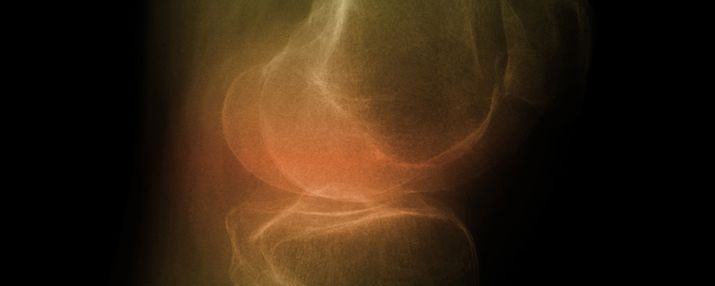

Operationen der Knie- und Hüftgelenke

Pro Jahr werden in den Bremer Kliniken rund 2.800 künstliche Hüft- oder Kniegelenke eingesetzt. Daher muss die medizinische Notwendigkeit von Eingriffen und die Produktqualität im Fokus stehen.

Durch unnötige Operationseingriffe oder mangelhaft hergestellte Prothesensysteme treten immer häufiger Komplikationen auf.